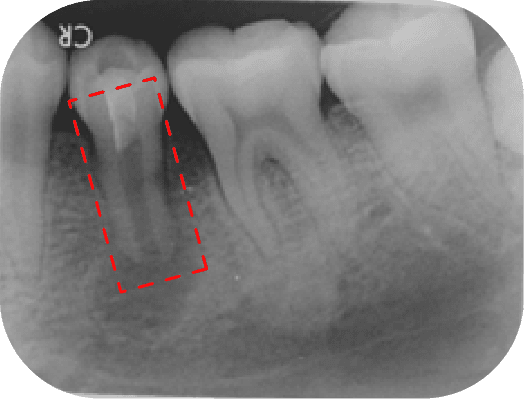

左圖中第一大臼齒兩個牙根皆因為根管內的感染造成根尖周圍炎(紅線中黑黑的地方),在根管治療後追蹤一年可發現骨頭都已經恢復正常的樣子

上圖中第一大臼齒兩個牙根皆因為根管內的感染造成根尖周圍炎(紅線中黑黑的地方),在根管治療後追蹤一年可發現骨頭都已經恢復正常的樣子